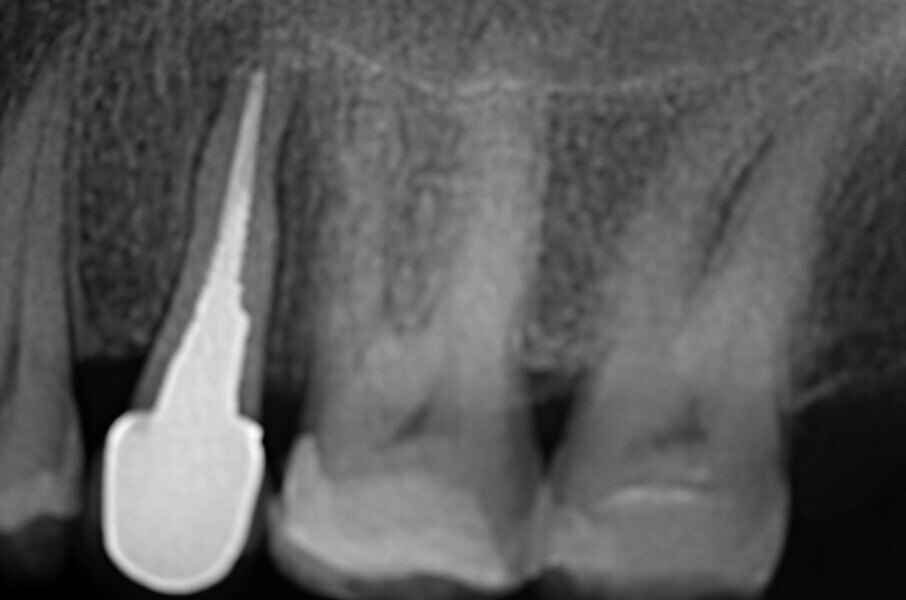

Fig. 44 : Radiographie de contrôle et excellente intégration de l’implant en céramique dans l’environnement parodontal.

Fig. 45 : Radiographie de contrôle et excellente intégration de l’implant en céramique dans l’environnement parodontal.

Un patient présentant un défaut infraosseux s’est présenté au cabinet dentaire avec le souhait explicite d’un traitement par un implant en zircone, pour remplacer l’une de ses molaires. Un implant deux pièces en zircone a donc été posé et le défaut infra-osseux a été traité dans le même temps, au moyen d’une allogreffe osseuse et du dérivé de matrice amélaire Emdogain (Straumann). La mise en charge n’a pas été réalisée à ce stade (Figs. 35–45).